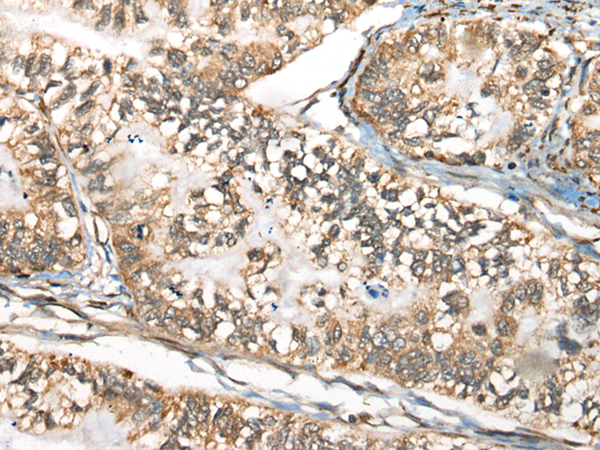

IHC positive control: |

Human liver cancer and human gastric cancer |